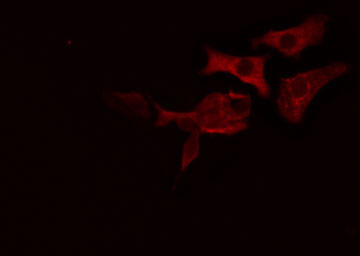

IF (Immunofluorescence)

(AAA324260 staining HT29 cells by IF/ICC. The sample were fixed with PFA and permeabilized in 0.1% Triton X-100, then blocked in 10% serum for 45 minutes at 25 degree C. The primary antibody was diluted at 1/200 and incubated with the sample for 1 hour at 37 degree C. An Alexa Fluor 594 conjugated goat anti-rabbit IgG (H+L) antibody, diluted at 1/600, was used as secondary antibody.)